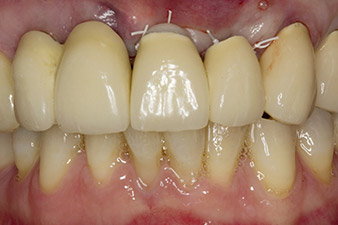

Ситуацията след имплантиране

Фиг. 6: Ситуацията след имплантиране и аугментация: Старият мост е поставен отново като временно възстановяване за фазата на заздравяване със свободно фрезован мост над имплант в позиция 22. Планираното перманентно възстановяване ще бъде с циркониево-оксиден мост от 12 до импланта, за да бъде поставен в позиция 23.

В това научно изследване, ситуацията е разрешена с имплант в позиция от първата процедура и допълнителен имплант на мястото на екстрахиран зъб 23 по-късно в хода на лечението. Вторият имплант е поставен след успешна остеоинтеграция на имплант 22. Ревизираният мост е поставен отново, докато имплант 23 заздравее на място и оформянето на перманентното възстановяване е завършено. Предимствата на този надграждащ подход включват възможността имплантите да понесат по-гъвкаво натоварването и пълноценно да се развият твърдите и меките тъкани (5).